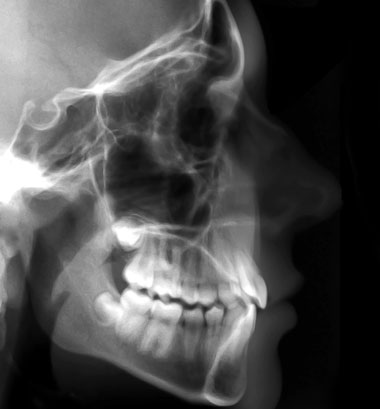

Une fois la consultation effectuée, le prochain rendez-vous est l'examen orthodontique. Durant ce rendez-vous nous allons prendre des photos de votre visage et de vos dents, des empreintes de vos dents et certaines radiographies pour évaluer vos bases osseuses et la relation de vos dents à votre mâchoire. Nous serons donc en mesure d'établir un diagnostic précis et complet. Votre traitement orthodontique commencera en moyenne 1 mois après l'examen orthodontique le temps que votre diagnostic et plan de traitement soit établit!